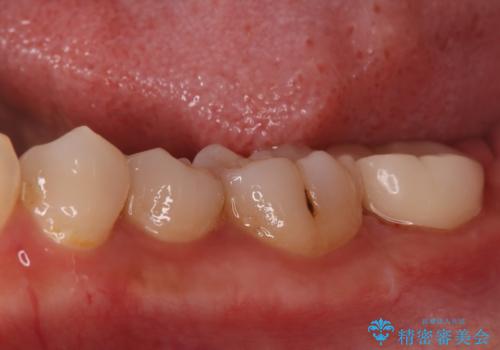

- 昨日からのズキズキとした激しい痛みを主訴にご来院されました。レントゲンおよび歯髄診察の結果、不可逆性の歯髄炎(歯の神経の重度の炎症)と診断。歯を残すことを第一に、まず痛みの原因である神経を取り除く根管治療を提案しました。また、虫歯が歯肉の下まで深く進行していたため、根管治療後に歯周外科処置を行い、最終的に精密なセラミッククラウンで修復する、総合的な治療計画を立案しました。

治療はまず、根管治療から始め、感染した神経を徹底的に除去することで、痛みをすぐに解消しました。再発を防ぐため、ラバーダムや顕微鏡を使って、根管内を丁寧に、そして精密に処置しました。次に、深い部分の虫歯を確実に治療するため、歯周外科処置を行い、治療しやすい環境を整えました。最後に、機能と見た目に優れたセラミッククラウンを作製・装着。根管治療から外科処置、審美修復までを一貫して行うことで、再発リスクの低い、長期的に安定して使える奥歯を取り戻していただけました。